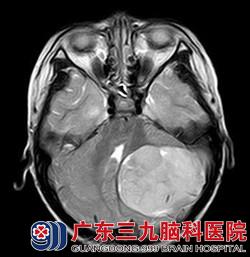

经华刚医生详细询问病史及查体后,明确患儿目前左侧小脑半球存在占位性病变。根据患者年龄结合头颅磁共振,考虑髓母细胞瘤可能性大,且病变已形成小脑扁桃体下疝,体征上已有不能走一字步,指鼻不准确、双手快速轮替运动差等症状。若肿瘤进一步生长,患者上述功能将进一步变差,甚至肿瘤严重压迫脑干,造成心跳呼吸骤停等风险。另外,因脑脊液循环通路因受肿瘤压迫,脑室内的脑脊液不能按正常途径回流,造成脑室内脑脊液过多、渗出,常常出现胡言乱语、大小便失禁、呕吐、精神反应变差等症状。患者需尽快行手术治疗,否则后果不堪设想。

看着生病的女儿情况一天比一天糟,小茹的父母心如刀割,但几万元的手术费用对一个务农的家庭来说是笔大数目。是放弃还是手术,小茹的父母内心苦苦挣扎着。在亲戚朋友劝说及帮助下,小茹父母终于筹到手术费用,为小茹办理了入院手续。接下来,医生们为小茹进行了“左侧小脑占位病变切除术+右额脑室外钻孔引流术”,术程顺利。术后病理示:髓母细胞瘤 WHO IV级。

广东三九脑科医院神经外八科华刚医生介绍,髓母细胞瘤好发于儿童,占儿童颅内肿瘤的近1/3,尤其10岁以前的小儿为发病高峰年龄。髓母细胞瘤早期症状较隐匿,一般出现头痛呕吐、步态不稳等中枢神经系统症状后才被发现。手术切除和术后放化疗是治疗该肿瘤必不可少的手段,手术应在保护脑干功能的情况下尽可能全切除肿瘤,并解决脑脊液循环通路受阻问题,解除肿瘤对脑干的压迫,避免术后脑积水,为术后短期内尽快实施放疗和化疗做好必要的准备。